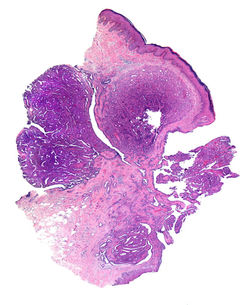

La condrodermatitis nodular del hélix (CNH) es una entidad inflamatoria benigna descrita por Winkler en 1915(1), agrupada dentro de las dermatosis con eliminación transepidérmica. Suele afectar el hélix de hombres entre la cuarta y sexta década de la vida, aunque en mujeres es muy característico el compromiso del antihélix (F1)(2). Clínicamente se describe como un nódulo pequeño solitario, de color pardo-violáceo, asociado a ulceración central (F1-F2)(1,2). Se considera excepcional el compromiso bilateral y en pacientes jóvenes(3).

Las características histológicas de la CNH dependen de la fase evolutiva de la lesión, presentando en etapas tempranas cambios muy inespecíficos con depósito de fibrina subepidérmica y cambios epidérmicos reactivos. En etapas finales se reconoce una lesión en cráter(F3) con un centro ulcerado que contiene abundante material fibrinoide eosinofílico que protruye hacia el exterior (F4,F5)(3,5). La base de la lesión presenta proliferación capilar y tejido de granulación, con trombosis, extravasación eritrocitaria e infiltrado linfohistiocitario variable(F7,F9). Adyacente a la úlcera, la epidermis muestra marcada acantosis y paraqueratosis(F6), con cambios reactivos sin atipia, además del acúmulo de fibrina subepitelial dscrito (F8)(5). Generalmente no se reconoce daño del cartílago auricular. El diagnóstico es sencillo con una adecuada correlación clínico-patológica, siendo necesario esta última para descartar los diagnósticos diferenciales.